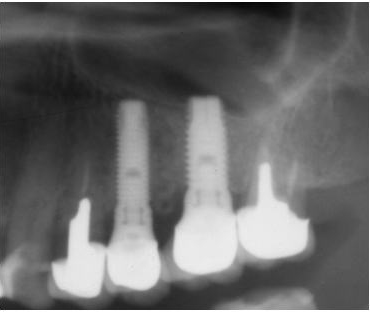

1.水平的骨吸収症例

下顎骨の後方部(下顎枝部)から採取した粉砕骨やブロック骨にて外側部の骨造成を行う。

2.垂直的骨吸収症例

下顎骨の後方部(下顎枝部)から採取したブロック骨にて歯槽頂部を再建する方法が、最も確実であり、当院では50例以上を行い、すべて良好な結果を得ている。